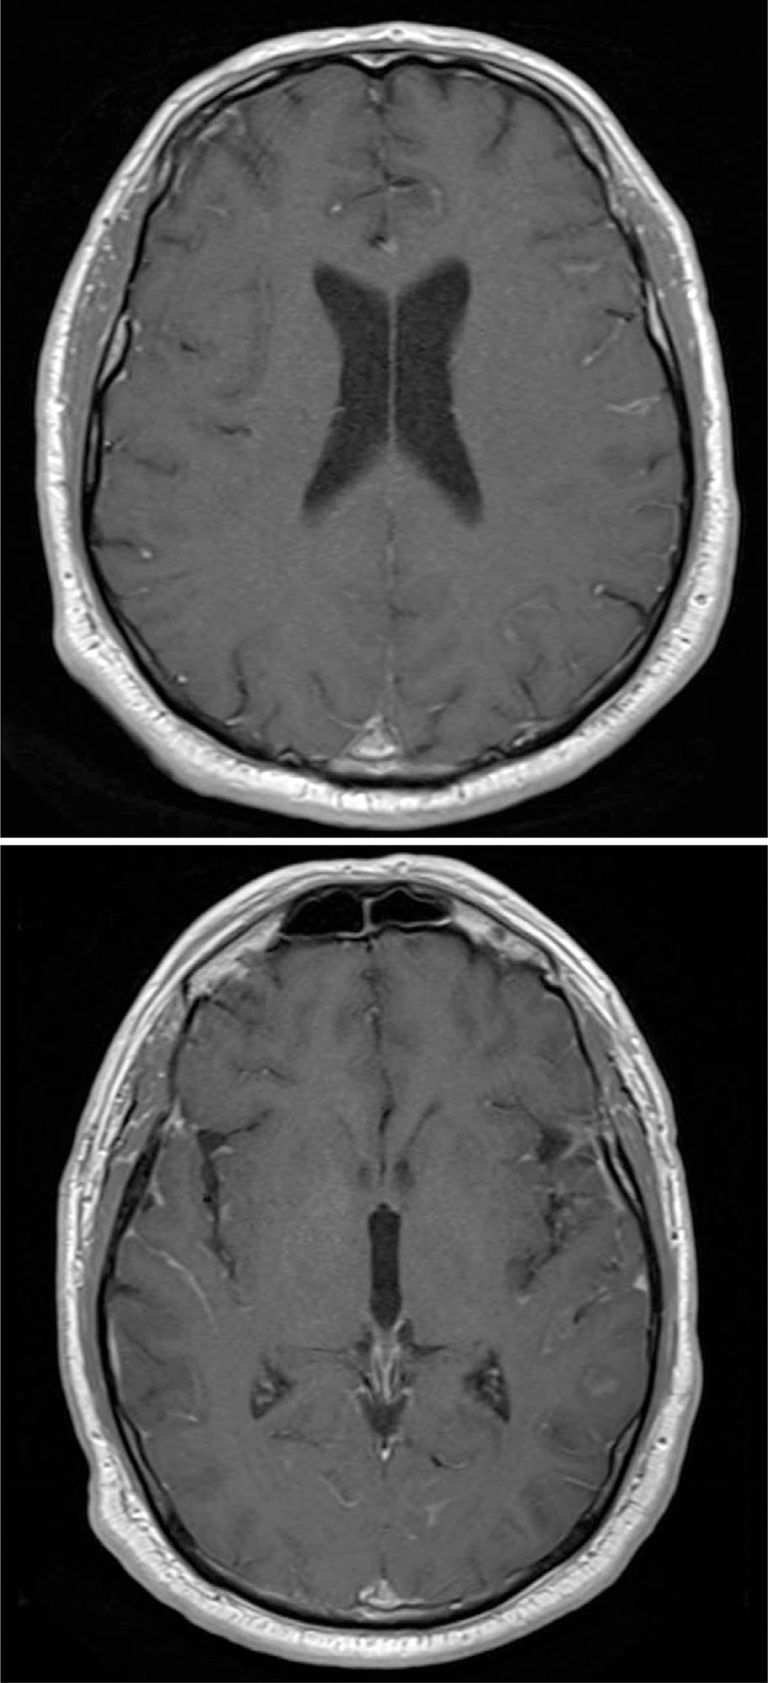

This report presents a case of a 59-year-old male diagnosed with metastatic esophagogastric junction adenocarcinoma, who presented with mild dysphagia and vertigo. Brain magnetic resonance imaging initially showed no abnormalities. Upper gastrointestinal endoscopy revealed a vegetative lesion in the distal esophagus, and concurrent colonoscopy identified a laterally-spreading tumor in the transverse colon. Immunohistochemistry confirmed a poorly differentiated adenocarcinoma, suggesting an upper gastrointestinal origin. Further investigation of the worsening neurological symptoms led to the identification of leptomeningeal carcinomatosis via cerebrospinal fluid analysis. Somatic genetic testing detected TP53 mutations and CDK6 amplification; however, no germline mutations were identified. The patient received first-line treatment with 5-fluorouracil, leucovorin, oxaliplatin, and nivolumab, followed by whole-brain radiotherapy due to rapid progression of the leptomeningeal disease. Despite aggressive treatment, the patient experienced multiple complications, including pulmonary embolism and seizures, and died from disease progression after six cycles of therapy. This case highlights the diagnostic challenges and poor prognosis of metastatic esophagogastric junction adenocarcinomas with de novo meningeal and colonic involvement and underscores the importance of early diagnosis and comprehensive evaluation of atypical presentations to optimize patient management.